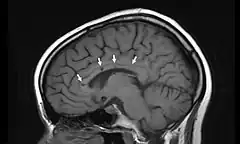

Vista lateral de una resonancia magnética nuclear de la cabeza. Las flechas indican la localización de microinfartos cerebrales característicos del síndrome de Susac.

El síndrome de Susac en una rara enfermedad descrita en 1979 por el neurólogo norteamericano John Susac. Es una microangiopatía que provoca la oclusión de los pequeños vasos sanguíneos que aportan sangre al cerebro, la retina y el oído interno. Técnicamente se describe como una microangiopatía que afecta a las arteriolas precapilares. Los síntomas principales son dolor de cabeza, déficit cognitivo, pérdida de memoria, dificultad para la marcha, pérdida de visión y disminución de la capacidad auditiva (hipoacusia). La causa es desconocida, pero se cree que está provocado por un fenómeno de autoinmunidad. El tratamiento se basa en la administración de agentes inmunosupresores que disminuyen la respuesta inmunitaria, entre ellos glucocorticoides, azatioprina y metotrexate.[1][2][3][4]